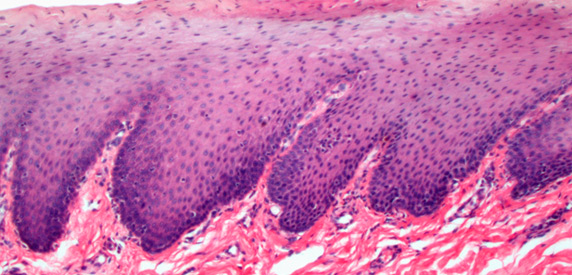

植入自体黑素母细胞后,黑色素可源源不断生成,均匀 着色。图为成活后的黑素母细胞电镜图。